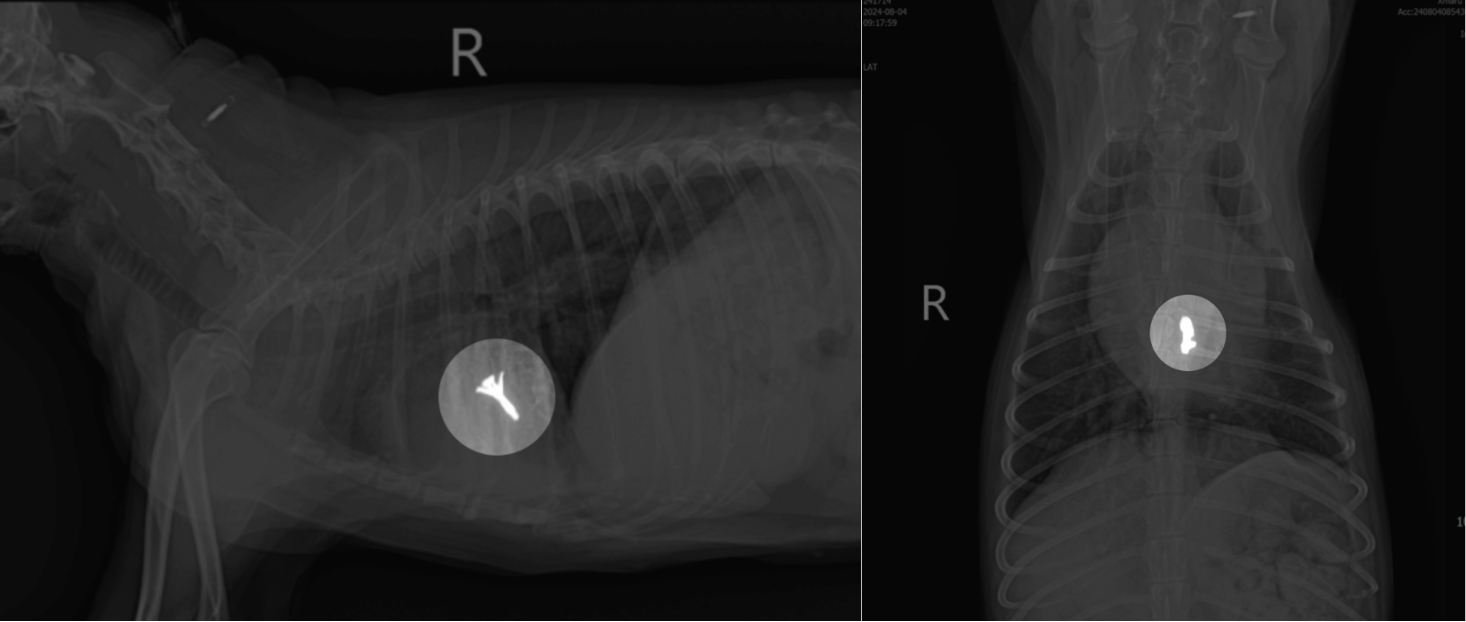

V-Clamp는 강아지 심장병 중 가장 높은 비중을 차지하는 ‘이첨판폐쇄부전증(MMVD)‘을 치료하는 최신 중재적 수술 기법으로 노화나 변성으로 인해 완전히 닫히지 않아 혈액이 역류하는 이첨판을 물리적인 ‘클램프(Clamp)‘로 튼튼하게 잡아주어, 혈액의 역류량을 즉각적이고 근본적으로 줄여주는 혁신적인 치료법입니다.

실제 V-Clamp 수술 환자 사례